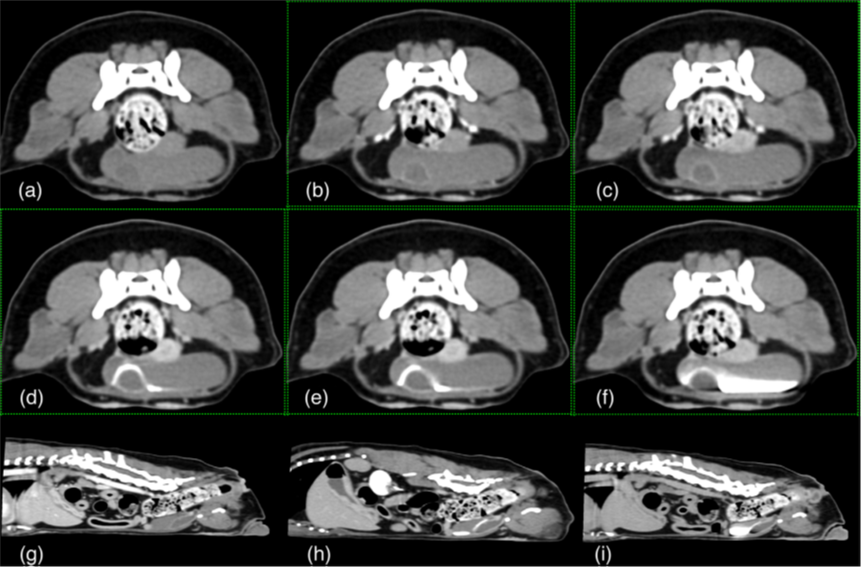

Tras una exhaustiva evaluación llevada a cabo mediante la combinación de Tomografía Computarizada con contraste, cistoscopia, radiografías y ecografía, se detectó que tenía una duplicación de vejiga en el plano coronal y una sola uretra, que además iba acompañada de una infección urinaria.

“La mayoría de los casos existentes acerca de la duplicación completa de la vejiga en el plano coronal también hablan de una duplicidad en la uretra. En este caso, sin embargo, la paciente solo tenía una uretra, conectada a la vejiga principal”, explica el equipo de Medicina Interna, Diagnóstico por Imagen y Cirugía de AniCura Ars que ha llevado a cabo tanto el diagnóstico como la extirpación quirúrgica de la vejiga duplicada.

Si la vejiga accesoria no cuenta con un uréter, retiene orina y no permite el acceso de los antibióticos, por lo que se crea un entorno ideal para el crecimiento bacteriano y la infección urinaria recurrente. “Cuando llegó a nuestro hospital, la paciente llevaba un año con infecciones de orina recurrentes, con recaída al terminar los antibióticos y con episodios intermitentes de disuria, polaquiuria y hematuria. Sin embargo, la exploración física era normal”, comenta el equipo que ha llevado con éxito el caso, formado por Jordi Puig, Luis Feo, Núria Vizcaíno, Elísabet Domínguez y Diana Gomes.